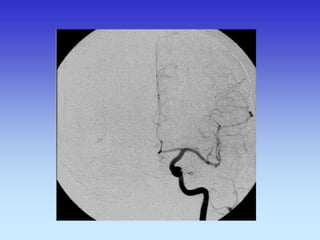

METODE PRIKAZA KRVNIH ŽILA

•UZ-DOPPLER

•DSA

•CTA

•MRA